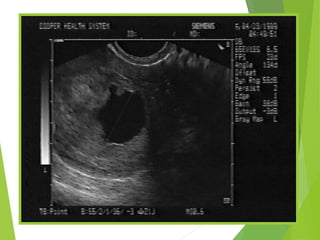

Definite IUP

 A gestational sac

with a sonolucent

center (greater

than 5 mm

diameter)

 Surrounded by a

thick, concentric,

echogenic ring

 GS contains a fetal

pole or yolk sac, or

both